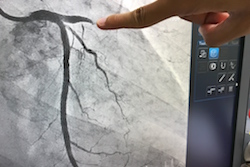

Forscher entwickelten eine von ihnen so bezeichnete „virtuelle Arterie“, ein Multiskalenmodell, das physikalische, chemische und biologische Daten umfasst. Das Team replizierte die Aktivität einzelner Zellen in der Arterienwand (Endothelialzellen und Zellen der glatten Muskulatur) und im fließenden Blut (rote und weiße Blutkörperchen sowie Thrombozyten). Dabei untersuchte es die Tunika media (die mittlere Schicht der Arterienwand aus Muskel und Gewebe), die sich im Modell aus kugelförmigen Zellen in einem dicht gepackten hexagonalen Gitter zusammensetzt. Zur Behandlung von Stenose – der abnormalen Verengung eines Blutgefäßes – werden häufig Ballonangioplastie angewandt und Stents gesetzt. Dies kann wiederum zur sogenannten „In-Stent-Restenose“ führen, dem Wachstum von Zellen der glatten von Muskulatur in einer Koronararterie, das weitere chirurgische Eingriffe erforderlich machen kann. Das Forschungsteam setzte sich zum Ziel, eine Möglichkeit zu finden, die Wahrscheinlichkeit statistisch vorherzusagen, mit der diese Nebenwirkung bei einem behandelten Patienten auftritt. Eine „virtuelle Arterie“ zur Modellierung einzelner Zellen und ihrer Interaktion Die von der EU teilfinanzierte Forschung wurde kürzlich in einer wissenschaftlichen Arbeit(öffnet in neuem Fenster) beschrieben, die über „Royal Society Publishing“ veröffentlicht wurde. In dem Paper wird erklärt, wie – nach vorherigen Anwendungen des Modells in zweidimensionalen Simulationen – die dreidimensionale Version nun anhand von Daten validiert wurde, die aus Versuchen stammten, die an sezierten Streifen von Tunika media durchgeführt wurden. Das Modellierungssystem des Forschungsteams behandelte einzelne Zellen glatter Muskulatur als untereinander interagierende Einheiten, wobei auch berücksichtigt wurde, dass einzelne Zellen jeweils ihren eigenen Zyklus durchlaufen. So konnten sie die mechanische und biochemische Umgebung der Zellen vollständiger abbilden. Die modellierten Dehnversuche wurden mit denen verglichen, die im Labor durchgeführt wurden, wo sezierte Tunika-media-Streifen der Länge nach sowie entlang ihres Umfangs gedehnt wurden. Neue Möglichkeiten dank hoher Rechenleistung Mithilfe dieses Modellierungsansatzes konnte das Team auch den Transport der Thrombozyten in Aneurysmen untersuchen, indem sie die mechanischen Eigenschaften roter Blutkörperchen und Thrombozyten simulierten und diese mit dem Fluss des Blutplasmas kombinierten. Derzeit arbeiten verbessern die Forscher die Weise, in der die biologischen und chemischen Daten einfließen, sodass sie die Vorgänge nachvollziehen können, die mit Thrombose zusammenhängen. Die Anwendbarkeit dieser Methodik für verschiedene biomedizinische Prozesse spiegelt die Ziele der EU-finanzierten Projekte COMPBIOMED und COMPAT wider, die zum Erreichen dieser Ergebnisse beitrugen. Das Projekt COMPBIOMED (A Centre of Excellence in Computational Biomedicine) wurde speziell dazu ins Leben gerufen, die steigenden Rechenkapazitäten von Hochleistungscomputern zu nutzen, um unser Verständnis von kardiovaskulären, molekülbasierten und neuromuskoskelletalen Vorgängen, die in der Medizin eine Rolle spielen, mittels genauerer Modellierungen zu vertiefen. Das übergeordnete Ziel besteht in der Entwicklung eines automatisierten Arbeitsablaufs, in dem Daten eines einzelnen Patienten eingegeben und verarbeitet werden können, um Vorhersagen zu treffen und so eine personalisiertere Medizin zu ermöglichen. Als eine der zentralen Herausforderungen, die diesen prädiktiven Modellen gegenüberstehen, ist die Schwierigkeit zu nennen, die Variablen zu replizieren, die in physikalischen, zeit- und ortsabhängigen Multiskalenprozessen eine Rolle spielen. Das Projekt COMPAT (Computing Patterns for High Performance Multiscale Computing) steuerte Erkenntnisse bei, die durch die wiederverwendbaren Algorithmen für Performance Multiscale Computing gewonnen wurden, die bis in den Exaflop-Bereich skaliert werden können (in dem mindestens eine Milliarde Milliarden Rechenoperationen pro Sekunde stattfinden). In diesem Projekt soll Software entwickelt werden, durch die mit Computersimulationen aussagekräftige Vorhersagen getroffen werden können. Weitere Informationen: COMPBIOMED-Projektwebsite(öffnet in neuem Fenster) COMPAT-Projektwebsite(öffnet in neuem Fenster)